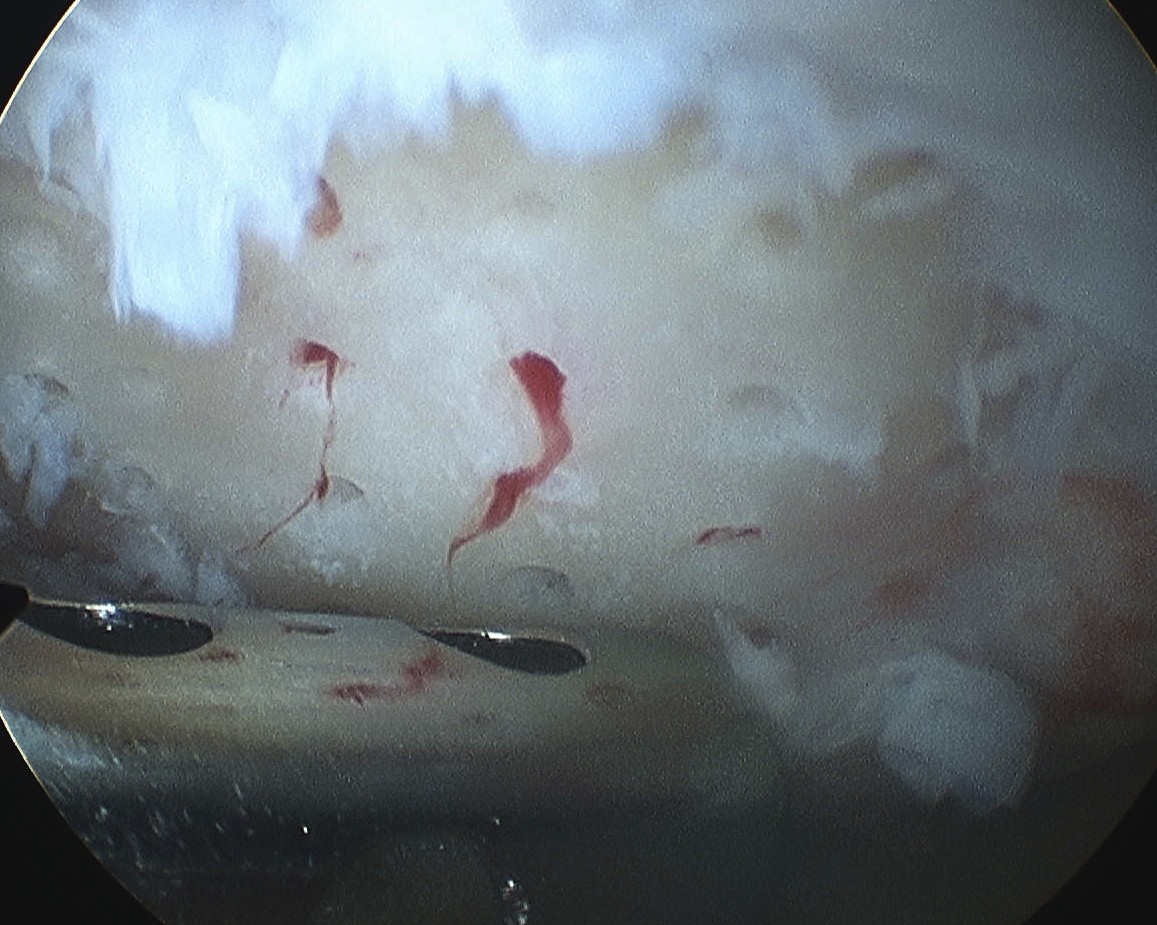

Debride all unstable cartilage to stable edge

- removed calcified cartilage layer with curette, protect subchondral bone

- create a perpendicular edge which helps to hold the clot

Fibrocartilage response to microfracture